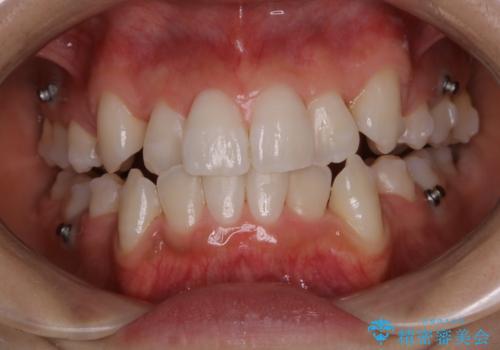

インビザライン中のエアーフロー

担当医 歯科衛生士